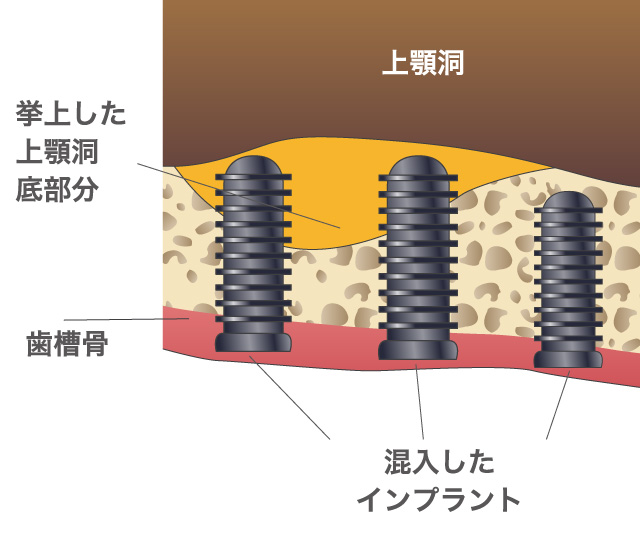

インプラント治療とは術前診査・診断を十分に行った上で、歯が抜けてしまった部分にインプラント(人工歯根)を埋め込み、その上から自然な見た目の人工歯を装着させるという治療法で、骨にしっかりとインプラント(人工歯)を定着させるため、自分の歯のようにしっかり、思い切り噛めるようになります。